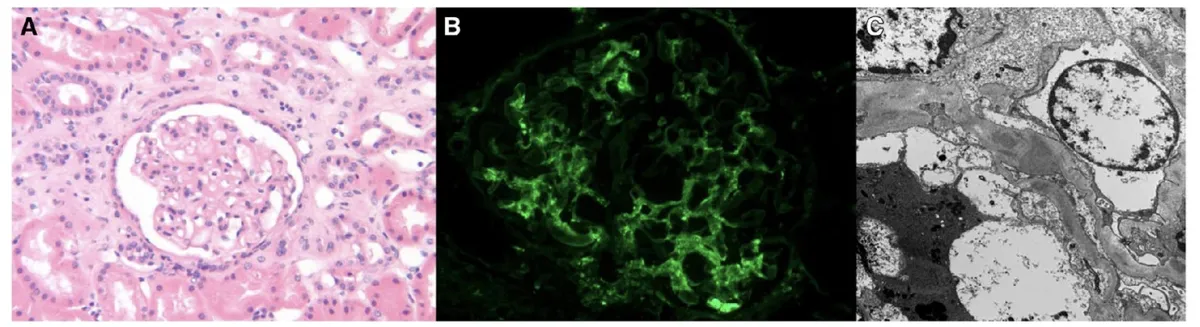

Figura 1. Imagens da biópsia renal. (A) Microscopia óptica mostrando hipercelularidade mesangial difusa, sem crescents, necrose ou cicatrizes segmentares. Discreta fibrose intersticial e atrofia tubular (HE). (B) Imunofluorescência evidenciando forte marcação de C3 no mesângio e nas alças capilares. (C) Microscopia eletrônica demonstrando depósitos mesangiais e depósitos subepiteliais maiores. Observa-se apagamento difuso dos pedicelos e afinamento das membrana basal glomerular (250 nm de espessura).

A presença de proteinúria moderada em paciente jovem, com imunofluorescência mostrando deposição dominante de C3 e depósitos densos à microscopia eletrônica, aponta para GNC3.

* Nefrite lúpica classe II: deposição mesangial isolada e padrão “full house” na IF (IgG, IgA, IgM, C3 e C1q), o que não ocorreu.

* GNPI: subepiteliais semelhantes, mas normalmente há infiltrado neutrofílico e IF positiva para IgG e C3. História familiar torna essa hipótese improvável.

* Nefropatia membranosa: também apresenta depósitos subepiteliais, mas com IF IgG- positiva.

* Síndrome de Alport: pode cursar com membrana basal fina, mas não com depósitos densos de C3.